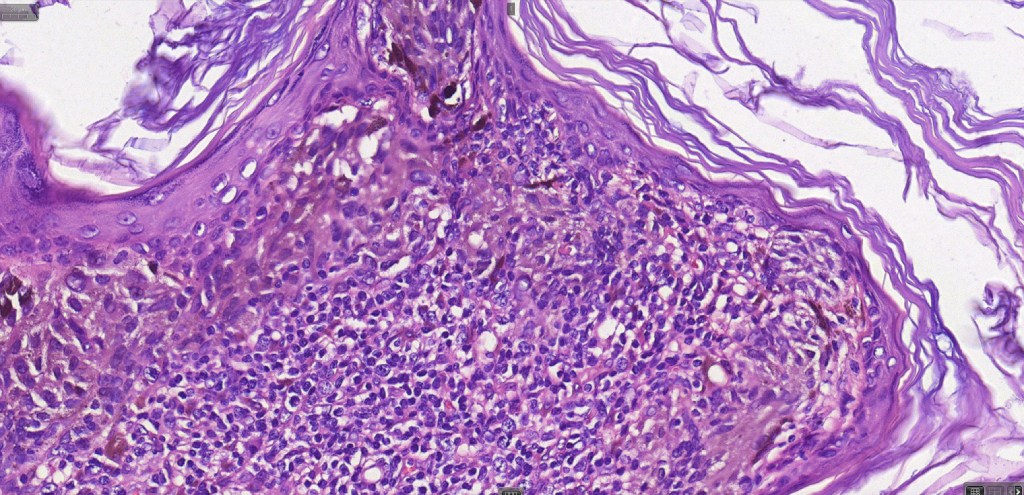

•Large dyscohesive nests with retraction artifact, not restricted to the tips of the epidermal ridges

•Bridging common, often over multiple rete ridges

•Variable atypia (can be marked)

•Central pagetoid spread

•Superficial dermal atypia

•Junctional mitoses sometimes present, dermal mitoses+/-, can be multiple but never atypical

•Dermal fibrosis (sometimes lamellar)